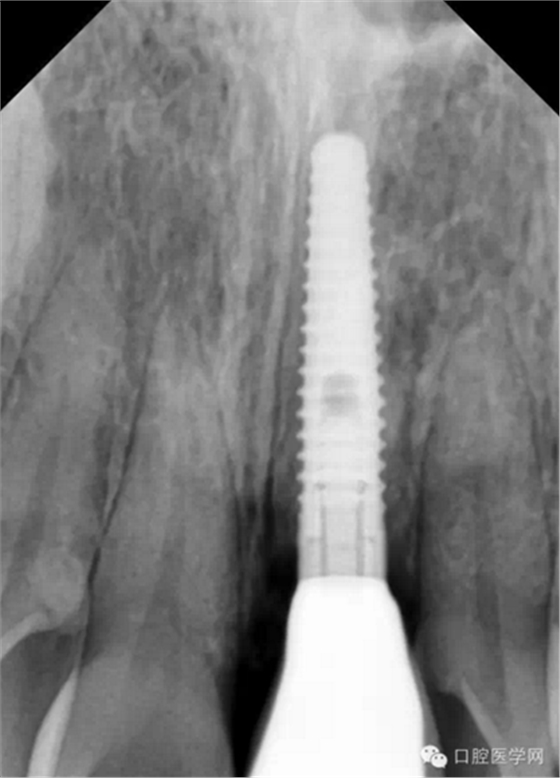

首先介绍一下最有特点的种植体,美国BICON种植体(美国百康种植体)

上面这张图片是百康种植体的照片,属于短种植体一类,独特的鱼嵴式设计是它最大的特点。

下面这张图片是百康种植体的X光片。